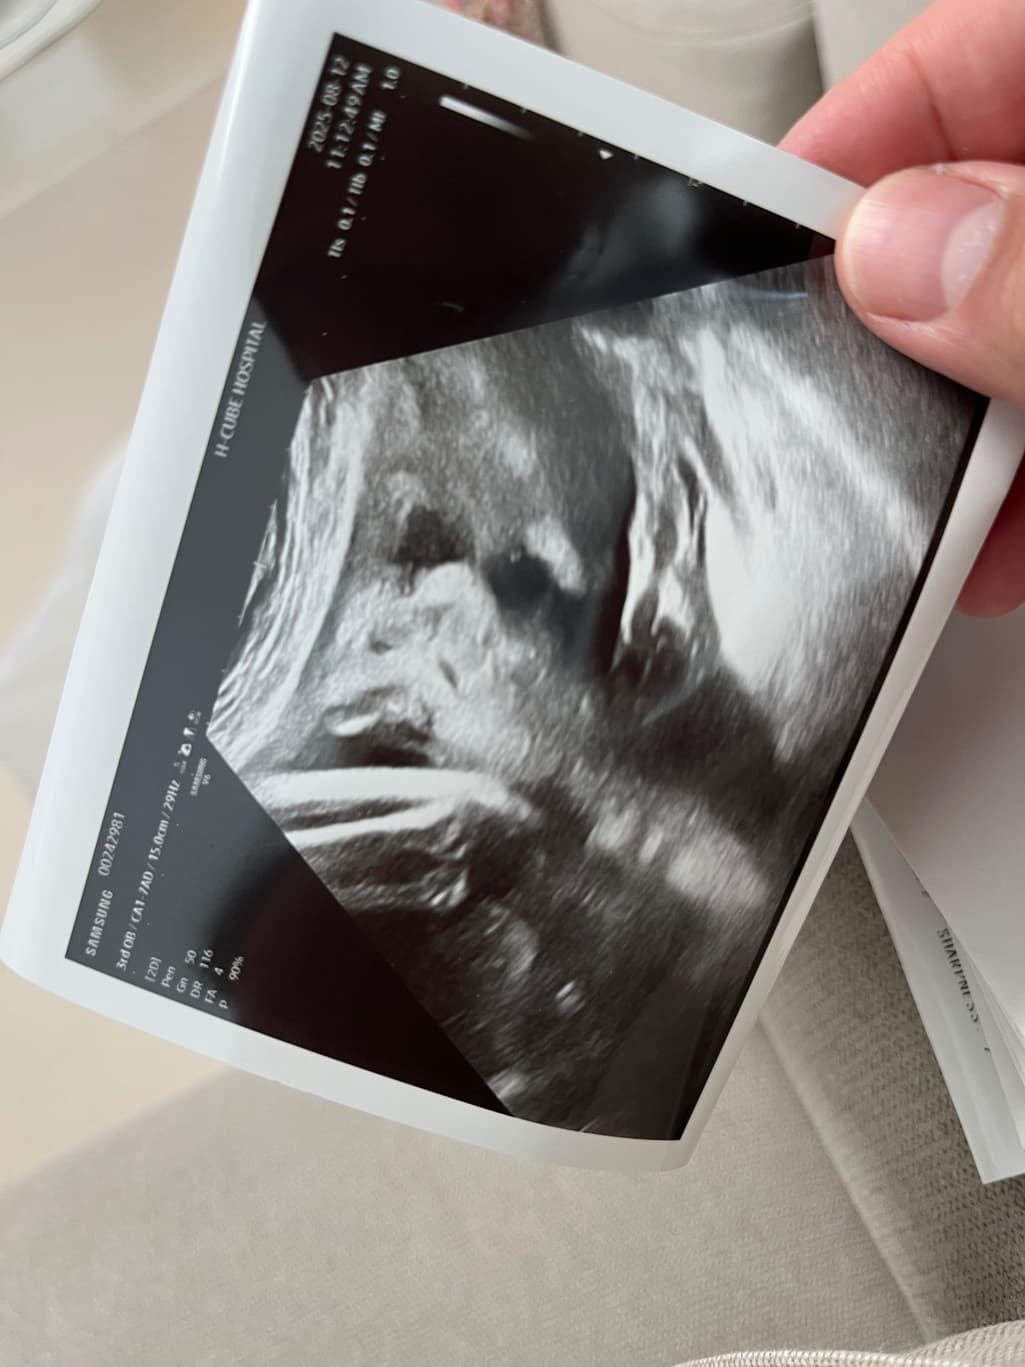

안녕하세요, 사진 순으로 24주차 입체초음파, 그 다음 두 장은 36주차 일반 초음파 사진입니다.

다름이 아니라 36주차 사진상 아이 눈 간격이 너무나 좁아보여서 걱정이 되어서 여쭈어봅니다..

옆으로 눌린 자세라 일시적으로 그렇게 보일 수 있는건지, 아니면 실제 저렇게 눈 간격이 좁은 아이의 경우도 있는지 궁금합니다.

초음파는 3차원의 물체를 2차원적 영상으로 표현하지요. 공간상 왜곡으로 보이며, 사실 특별한 소견으로 생각되지 않아요.

다운증후군일 경우에도 눈이 좁아보이거나 할 수 있지만, 이는 초음파로 눈의 간격을 확인하는 것이 아닌 목덜미 투명대, 심장구조 등을 보면서 평가하는 것이지, 질문자분이 걱정하시는 바가 아닙니다. 그리고 관련해서 문제가 있었다면 진즉에 담당 주치의가 설명을 했을 부분입니다.